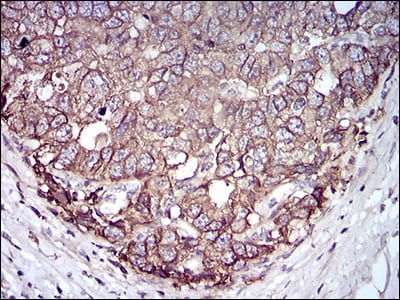

Immunohistochemical analysis of paraffin-embedded human cervical cancer tissues using EPCAM mouse mAb with DAB staining.